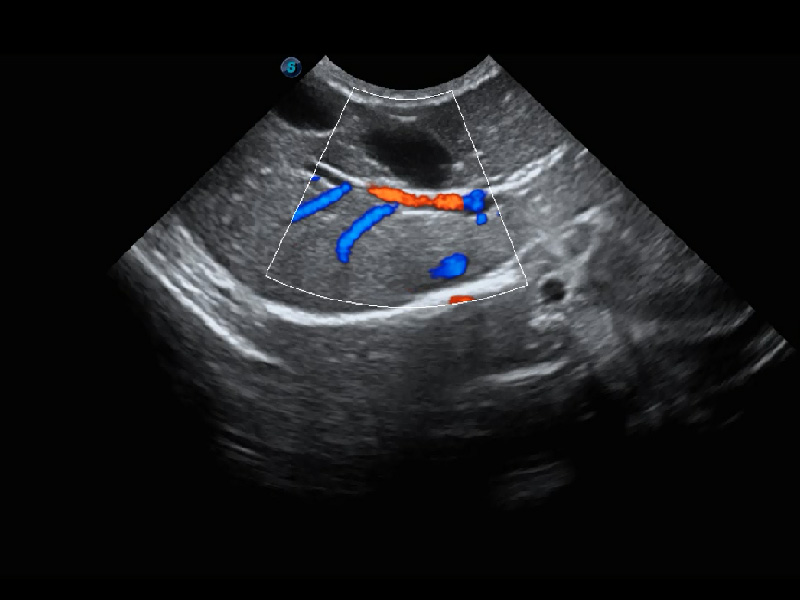

ProPet 60 作為一款高端臺式動物超聲設(shè)備,為動物醫(yī)生的日常診斷提供了一系列貼合動物臨床需求、解決臨床實際問題的高級成像功能。憑借全系列高清探頭,滿足醫(yī)生對腹部、心臟、生殖、淺表、肌骨等成像的所有需求,切實幫助您提升檢查效率,提高診斷信心。

動物是人類最親密的朋友和最值得信賴的伙伴。開立醫(yī)療也一直致力于探索動物專用的超聲影像解決方案。 全新推出的ProPet系列,是開立在動物超聲影像智能化、專業(yè)化、精準(zhǔn)化的一次跨越式革新。動物不能用言語來表述自己的不適,通過超聲影像,ProPet系列搭建了動物醫(yī)生與不同物種溝通的“橋梁”,為動物醫(yī)生注入了“治愈之力”。